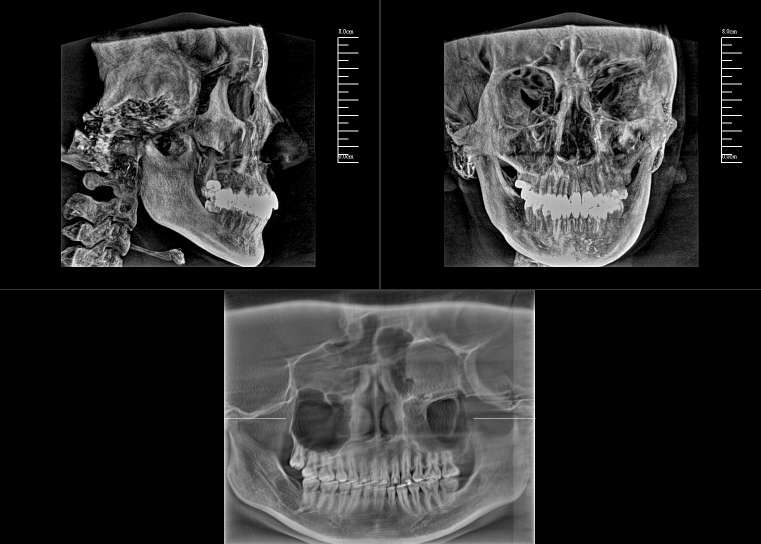

CBCT,全稱(chēng)“錐束計(jì)算機(jī)斷層掃描(Cone-Beam Computed Tomography,CBCT)”,由球管和平板探測(cè)器組成。與全科CT的閉環(huán)圓孔設(shè)計(jì)不同,數(shù)字化口腔CBCT采用開(kāi)放式結(jié)構(gòu)以保持其靈活性。

對(duì)于口腔內(nèi)科疾病,牙片和全景片已具有較高診斷效果;但對(duì)于牙體牙髓病,2D成像較容易發(fā)生影像重疊的情況,無(wú)法進(jìn)一步明確根管和其他周?chē)M織的三維信息,容易出現(xiàn)漏診或誤診根裂的情況。這就需要三維斷層成像,即數(shù)字化口腔CBCT。

數(shù)字化口腔CBCT是從三維的角度,即矢狀位、冠狀位和橫斷位來(lái)顯示病變組織和正常組織結(jié)構(gòu),有效的避免了2D圖像固有的缺陷,如正常組織器官的影像重疊,投射角度變化所致的影像扭曲、變形等,大大提高了診斷能力。

數(shù)字化口腔CBCT能在十幾秒時(shí)間內(nèi)完成患者口腔掃描,進(jìn)而生成高精度的三維影像,徹底解決了牙片機(jī)、全景機(jī)等傳統(tǒng)口腔X射線(xiàn)設(shè)備影像重疊、畸變的問(wèn)題??梢?60°全方位立體觀(guān)測(cè)牙床的骨質(zhì)密度、牙槽骨本身的高度、寬度等數(shù)據(jù),不僅能重建整個(gè)顱面區(qū)的結(jié)構(gòu),對(duì)頜面骨質(zhì)結(jié)構(gòu)進(jìn)行測(cè)量,而且還能重建精細(xì)的解剖細(xì)節(jié)。